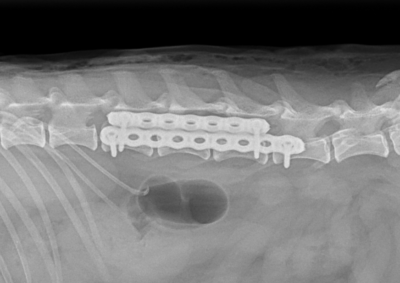

脳神経外科 注意 ボタンをクリックした先に、治療中および手術中の画像が説明で使用されている場合がございます。 そのような画像に弱い方は閲覧なさらないようお願いいたします。 脳神経外科 セメントレス環軸固定術 脳神経外科 Hemi-Laminectomy 脳神経外科 Ventral Slot 脳神経外科 椎体固定術 脳神経外科 Hemi-Laminectomy 脳神経外科 脊髄亜膜下憩室切除 脳神経外科 椎間板ヘルニア G1 脳神経外科 椎間板ヘルニア G2 脳神経外科 IVDD G5 脳神経外科 Ventral Slot 脳神経外科 Ventral Slot 脳神経外科 Ventral Slot 123456> 症例カテゴリー 放射線治療整形外科軟部組織外科脳神経外科内科腫瘍外科救急・集中治療リハビリテーション科腫瘍内科内視鏡科脳神経科呼吸器外科中医・漢方猫の腎移植循環器科電気化学療法